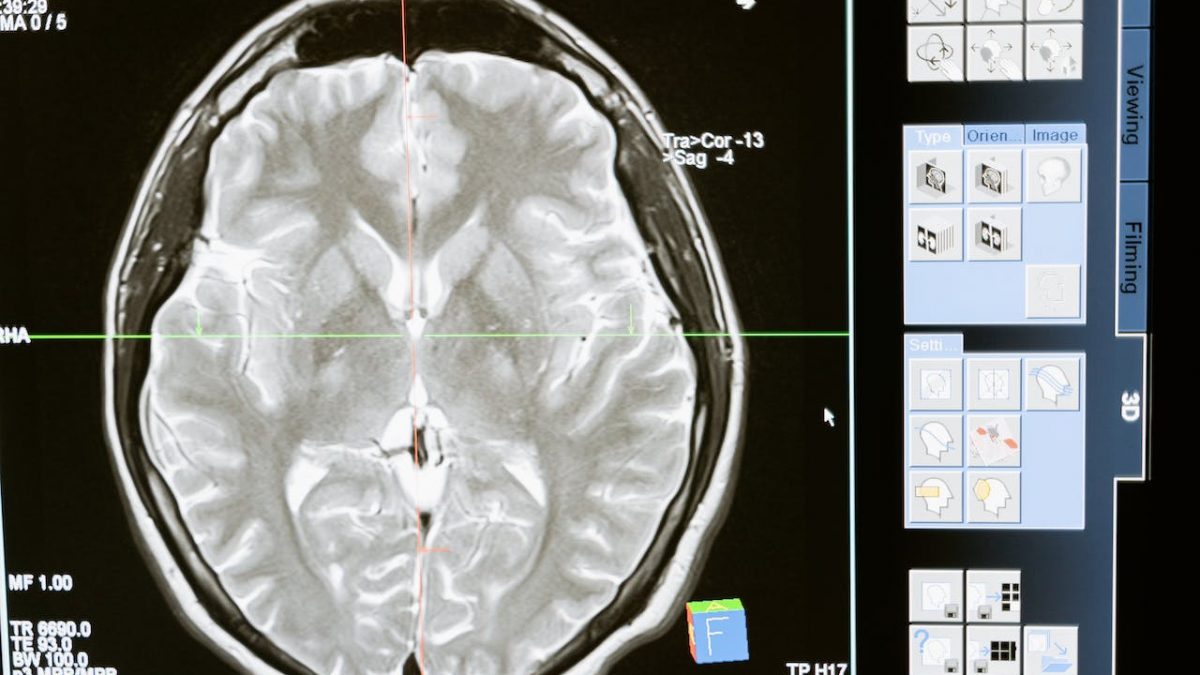

Dados recentes do estudo internacional Global Burden of Disease indicam que o número global de mortes por AVC isquémico subiu de 2,04 milhões em 1990 para 3,29 milhões em 2019, sendo previsto que este valor cresça para 4,90 milhões até 2030, indica a SPAVC numa informação enviada hoje à agência Lusa.

Sendo o AVC a principal causa de morte e incapacidade em adultos em Portugal, a educação pública torna-se fundamental para ajudar a população a reconhecer e agir adequadamente em caso de AVC, alerta a associação.

A sensibilização da população para as consequências do AVC, o conhecimento consistente dos principais fatores de risco modificáveis (sedentarismo, obesidade, hipertensão arterial, tabagismo, fibrilhação auricular, diabetes e consumo excessivo de bebidas alcoólicas) e não modificáveis (fatores genéticos individuais, hereditariedade, idade, raça ou sexo) e os sinais de alerta (desvio da face, falta de força num braço, dificuldade em falar) “são desde sempre uma prioridade da SPAVC”, que reforça a mensagem de que, perante sintomas de acidente, deve ligar-se para o número de emergência 112, ativando a Linha Verde do AVC.